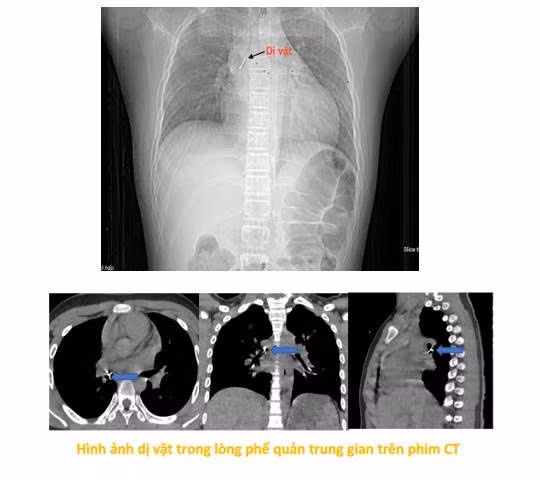

Tại đây, bệnh nhi được làm các xét nghiệm máu, chụp phim cắt lớp vi tính lồng ngực, nội soi phế quản ống mềm, các bác sĩ xác định dị vật đã nằm sâu trong phế quản trung gian bên phải.

Do dị vật sắc nhọn, đâm xuyên thành phế quản gây chảy máu và phù nề niêm mạc nên việc gắp gặp rất nhiều khó khăn. Sau hơn 2 giờ thực hiện thủ thuật không thành công, bệnh nhi được chuyển khẩn cấp sang Bệnh viện Phổi Trung ương.

Tiếp nhận ca bệnh, ThS.BSCKII Nguyễn Lê Nhật Minh, Trưởng khoa Nội soi chẩn đoán và can thiệp cùng ê-kíp đã nhanh chóng tiến hành thủ thuật nội soi phế quản ống mềm gắp dị vật để xử trí.

“Dị vật là chiếc đinh ghim sắc nhọn, nằm vướng tại phế quản trung gian, đầu nhọn đâm xuyên sâu vào thành phế quản. Đây là ca gắp dị vật rất khó, bởi ngoài tính chất, đặc điểm của dị vật như trên, bệnh nhi còn phản ứng theo phản xạ nên cần đòi hỏi thao tác nhanh, chính xác tuyệt đối để tránh làm rách thành phế quản hay đẩy dị vật xuống sâu hơn, có thể dẫn tới nhiễm trùng, chảy máu, tràn khí màng phổi, tràn khí trung thất. Thậm chí những biến chứng đó có thể gây hậu quả suy hô hấp cấp cho người bệnh.

Do vậy sau khi đã đánh giá toàn diện kíp thực hiện đã cẩn trọng gỡ phần đầu đinh đang cắm vào thành phế quản thành trạng thái tự do bằng những dụng cụ kìm nội soi phế quản chuyên dụng, rồi từ từ gắp thành công dị vật ra ngoài. Quá trình diễn ra trong vòng 15 phút”, bác sĩ Minh cho biết.